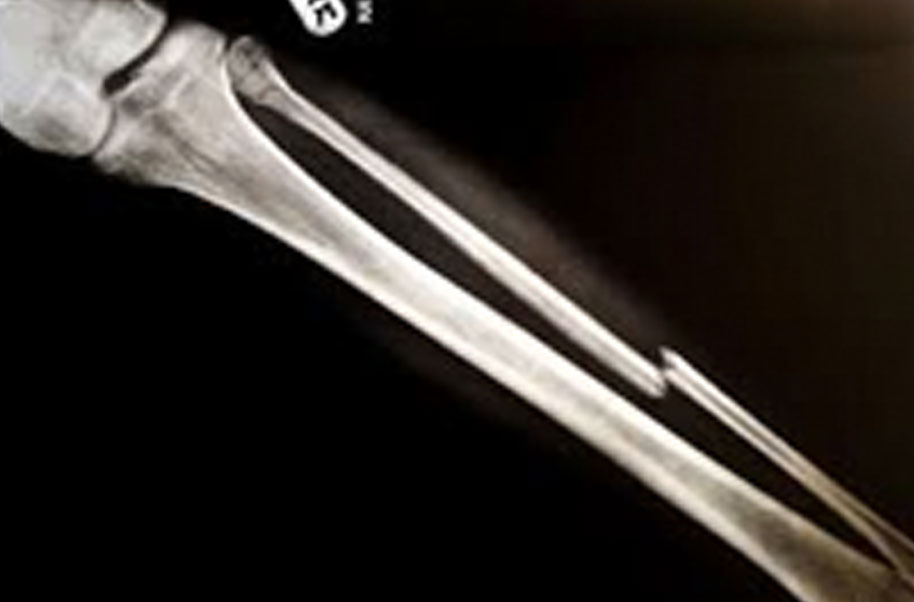

Ossiculum (Broken Bone)

A complete or partial break in a bone.

- Treatment often involves resetting the bone in place and immobilising it in a cast or splint to give it time to heal. Sometimes, surgery with rods, plates and screws may be required.

Causes of bone fractures include trauma, overuse and diseases that weaken bones.